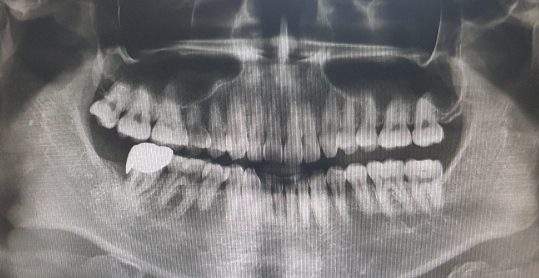

현재 파노라마 방사선 사진으로 보아 만성 치주염의 상태가 맞습니다. 잇몸뼈가 많이 안 좋아 보이고 특히 크라운이 씌워져 있는 오른쪽 아래(40번대)가 안좋아 보입니다. 뼈 높이가 다소 내려간 상태에서 이를 완전히 회복시키거나 하는 치약이나 보조제(약)은 없습니다. 다만, 치약 중에 잇몸에 좋은 생약성분이 포함된 치약이 있으니 그런걸 사용하면서 꾸준히 잇몸치료를 치과에서 받으시기 바랍니다.

한가지 더 말씀드리자면 작은 방사선 사진(치근단 사진)이 없고 파노라마 방사선 사진의 화질이 좋지 않아 정확히 말씀을 드리지는 못하지만 크라운을 한 쪽의 첫번째 큰 어금니(46번)와 두번째 작은 어금니(45번) 충치가 의심되며 크라운의 끝부분 모양과 높이가 이상적이진 않습니다. 다소 높이가 안 맞아서 잇몸에 좋지 않은 자극을 줄 수 있게 생겼는데 이건 단순히 교합조정으로 해결되지는 않습니다. 변화된 잇몸 모양이 맞춰 다시 크라운을 제작하는 것도 한번 고려해보시기 바랍니다.